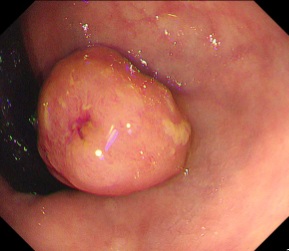

Polyps are early cancer indicators, so assessing occurrences of polyps and their removal is critical. They are observed through a colonoscopy screening procedure that generates a stream of video frames. Segmenting polyps in their natural video screening procedure has several challenges, such as the co-existence of imaging artefacts, motion blur, and floating debris. Most existing polyp segmentation algorithms are developed on curated still image datasets that do not represent real-world colonoscopy. Their performance often degrades on video data. We propose a video polyp segmentation method that performs self-supervised learning as an auxiliary task and a spatial-temporal self-attention mechanism for improved representation learning. Our end-to-end configuration and joint optimisation of losses enable the network to learn more discriminative contextual features in videos. Our experimental results demonstrate an improvement with respect to several state-of-the-art (SOTA) methods. Our ablation study also confirms that the choice of the proposed joint end-to-end training improves network accuracy by over 3% and nearly 10% on both the Dice similarity coefficient and intersection-over-union compared to the recently proposed method PNS+ and Polyp-PVT, respectively. Results on previously unseen video data indicate that the proposed method generalises.